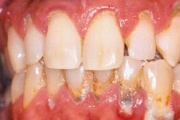

Krooniline parodontiit

Krooniline parodontiit on mikroobide poolt põhjustatud hammaste tugikudede põletik, mille tulemusena tekib progresseeruv alveolaarluu (nähtav röntgenograamil) ja periodontaalligamendi destruktsioon, igemetaskute moodustumine, igeme retsessioon või mõlemad kahjustused kombineeritult. Loe edasi »

- igemepealne hambakivi (5)

- igemealune hambakivi (4)